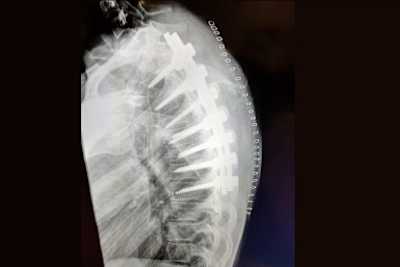

Nun veröffentlichte Carrasco in den sozialen Medien ein Röntgenbild ihrer Wirbelsäule, das das wahre Ausmaß des Eingriffs zeigt. Angesichts der langen Narbe konnte man bereits erahnen, dass die Verletzung umfangreicher war: Auch für einen medizinischen Laien ist erkennbar, dass die 300er-Weltmeisterin von 2018 gleich an sieben Brustwirbel operiert wurde, die durch eine Platte miteinander versteift sind. "Ich habe gezögert, dieses Bild von meinem Rücken nach der Operation zu veröffentlichen", gestand Carrasco. "Ich lade sie vor allem hoch, um die Arbeit von Dr. Ubierna und seinem Team zu würdigen. Dank ihrer Arbeit werde ich in ein paar Monaten wieder fit sein!" Ob das Metall vor der Saison 2021 entfernt wird und ob Carrasco auf dem Motorrad eingeschränkt sein wird, bleibt abzuwarten. Die tapfere Jura-Studentin – und auch Kawasaki – traut es sich zu: Am Mittwoch wurde die Vertragsverlängerung um ein Jahr bekannt gegeben.